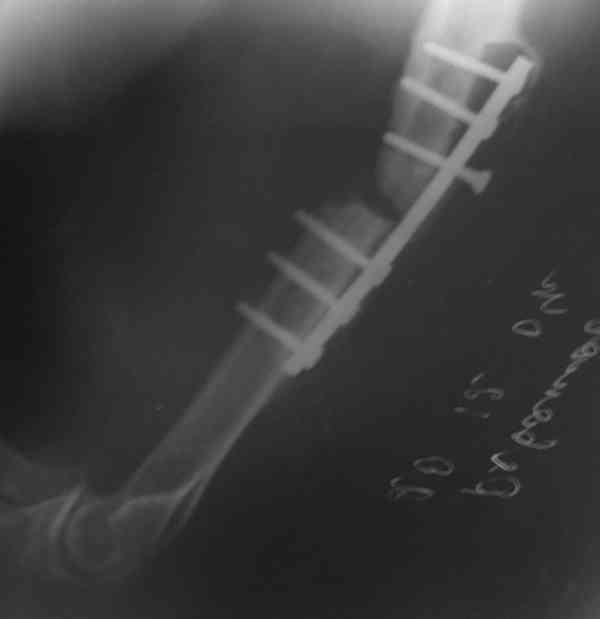

Мы бы предложили БИОС ретроградно (хотя это не принципиально, можно и сверху). Учитывая,что ложняк "болтающияся", больших трудностей с закрытым вскрытием канала (в зоне ложного сустава) быть не должно. Конечно нужен инструмент: сначала длинная (350-400 мм) острая спица (шило)диаметром 4-5 мм., затем гибкие развертки до 8-9 мм и соответствующий массивный штифт...

Штифт - отвисание проксимального отдела - накостный остеосинтез, нагноение, АФВ с ревизиями раны, опять пластина и снова нестабильность. Была удалена пластина и выполнен БИОС штифтом ChM (ДЕОСТ). Через 2 нед. пациент сел за руль и вышел на работу. Причем так и работает до сих пор уже 1,5 года, хотя полного сращения мы вроде бы не достигли ( снимки пришлю позже) - пациент не приходил на осмотры, общался только по телефону.